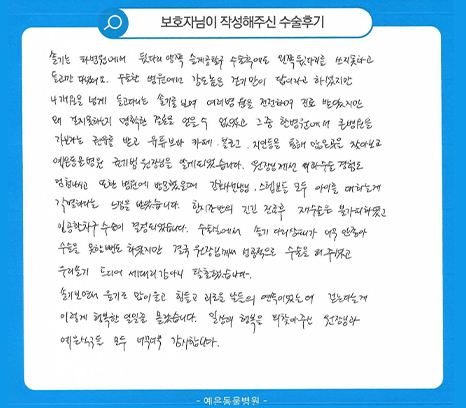

치료 후기

솔기는 타병원에서 뒷다리 양쪽 슬개골 탈구 수술 후에도 왼쪽 뒷다리를 쓰지 못하고 들고만 다녔어요. 수술한 병원에선 강도 높은 걷기만이 답이라고 하셨지만 4개월을 넘게 들고다니는 솔기를 보며 여러 병원을 전전하며 진료 받았지만 왜 걷지 못하는지 명확한 결론을 얻을 수 없었고 그 중 한 병원에서 큰 병원을 가보라는 권유를 받고 유튜브나 카페, 블로그, 지인 등을 통해 많은 곳을 찾아보고 예은동물의료센터 권기범 원장님을 알게되었습니다. 원장님께선 외과수술 경험도 엄청나시고 또한 병원에 방문했을 때 간호사 선생님, 스텝분들 모두 아이를 대하는게 각별하다는 느낌을 받았습니다. 한시간 반의 긴긴 진료 후 재수술은 불가피하였고 인공활차구 수술을 결정하게 되었습니다. 수술실에서 솔기 다리상태가 너무 안좋아 수술을 못할 뻔도 하였지만 결국 원장님께서 성공적으로 수술을 해주셨고 우리 솔기 드디어 세다리 강아지 탈출했습니다. 솔기보면서 울기도 많이 울고 힘들고 괴로운 날들의 연속이었는데 걷는다는게 이렇게 행복한 일일줄 몰랐습니다. 일상의 행복을 되찾아주신 원장님과 예은 식구들 모두 너무너무 감사합니다.